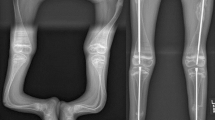

Patients with osteogenesis imperfecta, especially the moderate to severe types, require frequent surgical intervention. Anesthetic management and post-operative pain management benefit from careful preparation and a multimodal analgesic approach. Perioperative challenges that are of primary concern for anesthesiologists include airway challenges, intravenous catheter placement challenges, neuraxial and regional anesthesia placement difficulty, and significant intraoperative blood loss. Historical concern for malignant hyperthermia has been refuted and will not be discussed. Airway management may be difficult because of facial dysmorphism, macroglossia, megalocephaly, cervical instability, a short neck, and thoracic kyphoscoliosis with pectus carinatum. These skeletal abnormalities, along with frequent fractures, lead to bony protrusions and irregular bony landmarks that may make neuraxial and regional anesthesia more challenging. An additional perioperative concern is the potential for osteogenesis imperfecta patients to sustain additional fractures while undergoing surgery and anesthesia. Careful planning is required to successfully manage OI patients and the anesthetic challenges they pose and avoid complications in these fragile patients.